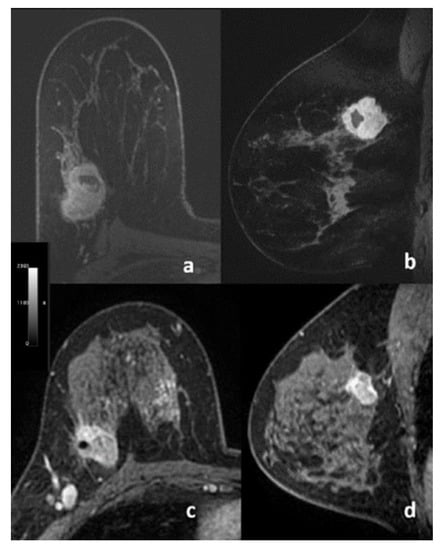

2.5. Radiomics Analysis

3.2. Radiomics Analysis and ML